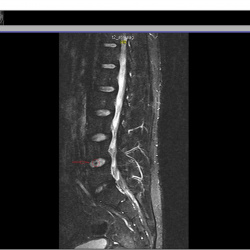

Здравствуйте. Постоянная боль в пояснице справа. Есть протрузия нижнего диска,  врач говорит, что она не должна болеть т.к. маленькая. Листая снимки заметил на соседнем диске какяю-то вертикальная полоса и темное пятно при пролистывании. Это норма или что-то ещё?